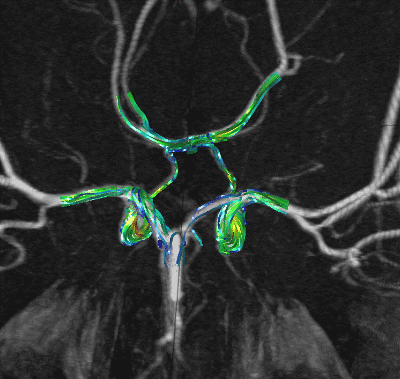

This example shows the combination of traditional flow visualization with volume rendering techniques. In this case the blood flow in the circle of Willis was computed in a realistic model reconstructed from contrast-enhanced magnetic resonance angiographic (MRA) images.

Finally the calculated streamlines are displayed simultaneously with the volume rendering of the anatomical images.